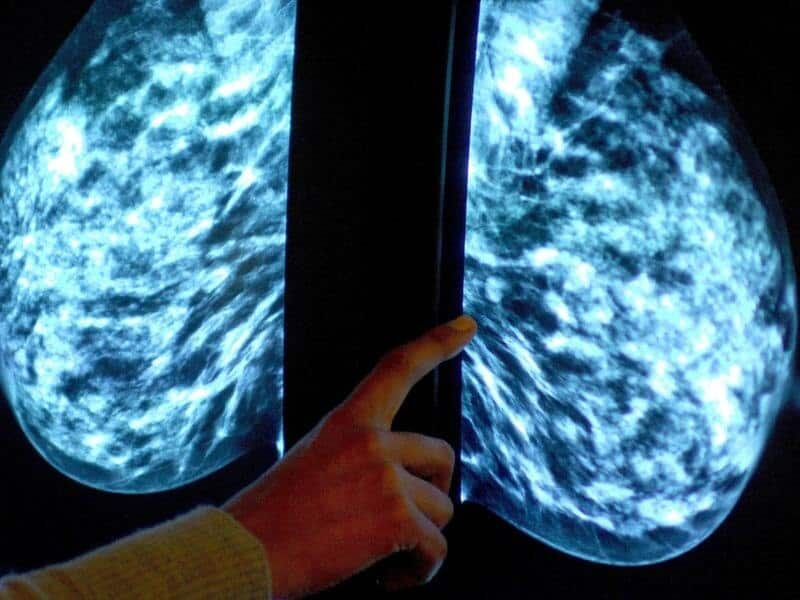

हरेक आठ मध्ये एक महिलामा देखिने स्तन क्यान्सर, अस्ट्रेलियामा सबैभन्दा बढी देखिने क्यान्सरको प्रकार हो। यहाँ सन् २०१८ मा, करिब १८ हजार महिला र १ सय ४० पुरुषहरू स्तन क्यान्सर बाट पीडित भएको बताइन्छ।

पहिलो चरणमा नै स्तन क्यान्सर पत्ता लगाएर उपचारमा सहयोग पुर्याउन नियमित स्तन जाँच गर्नुपर्ने बारे नेपाली लगायतका महिलाहरूमा जनचेतनाको अभाव रहेको छ।

क्यान्सरले हुने गरेको महिला मृत्युको सबैभन्दा बढी कारणहरूमा स्तन क्यान्सर दोस्रो स्थानमा रहँदा, ५० देखि ७४ वर्ष उमेर समूहका महिलाहरूलाई हरेक दुई-दुई वर्षमा स्तन जाँच्न प्रोहत्सान गर्ने सरकारी नीति रहेको छ।

स्तन क्यान्सर भएको प्राथमिक चरण वा शून्य चरणमा नै पत्ता लागे यसको उपचार सम्भव भएका कारण नियमित स्तन परीक्षण गर्न महिलाहरूलाई प्रोत्साहन गरिएको हो।

ब्रेस्ट स्क्रिन अस्ट्रेलियाले महिलाहरूलाई हरेक दुई वर्षमा निःशुल्क स्तन जाँच अर्थात् मामोग्राम गराउने व्यवस्था गरिदिएको भए पनि अपेक्षित रूपमा महिलाहरूको सहभागिता नभएको जानकारहरू बताउँछन्।